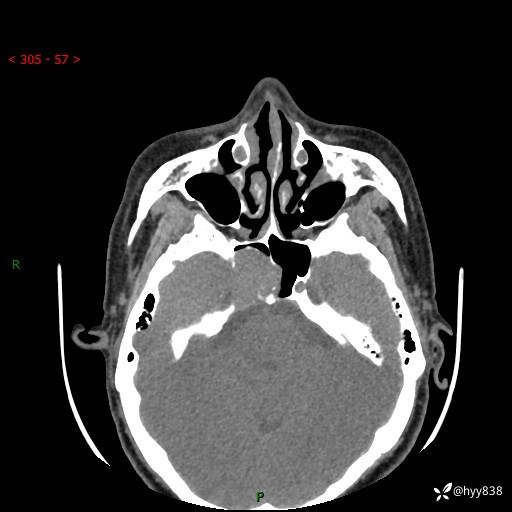

蝶鞍CT平扫